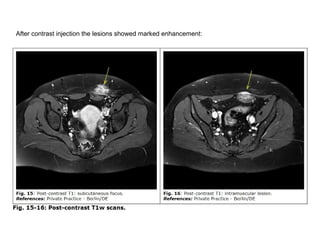

After contrast injection the lesions showed marked enhancement:

The MRI appearance of the lesions ruled out an abscess

and confirmed the similarity of the intramuscular and

subcutaneous foci. It further suggested subacute and

chronic micro-hemorrhaging within the lesions, possibly

consistent with hypervascularized tumors such as

melanoma or soft tissue sarcoma but also with ectopic

endometrial tissue islands, i.e. endometriosis.